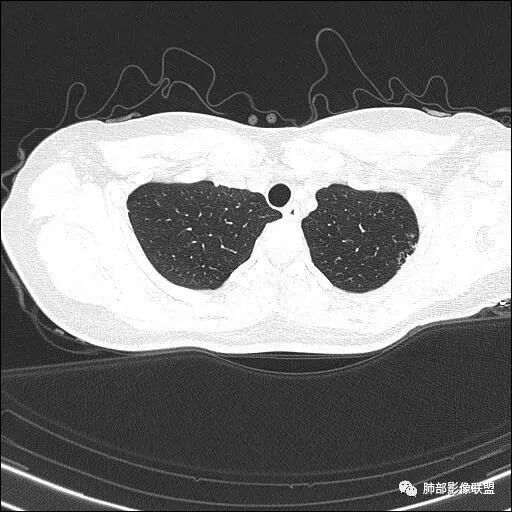

【每日晨读】双肺上叶多发薄壁空洞

双肺上叶多发结节影及纤维索条影,部分结节内部可见空洞形成,形态欠规则,洞壁厚薄均匀,以胸膜下分布为主,多灶性,多态性,临床年轻女性,体检发现,考虑结核,寄生虫?NTM.

双肺上叶尖段分布为主多发囊腔伴斑点,斑片影,囊腔壁不规则,部分内见分隔。考虑结核可能

两肺多发囊或空洞(部分腔内不干净可见间隔影)+多发结节 (右侧胸膜下的结节显著)+左肺尖斑片影。年轻女性,体检发现。考虑结核?鉴别PLCH(奇异囊加结节,吸烟男性多见),转移瘤(要有原发肿瘤病史)

2.双肺多发薄壁空洞影、条索影及结节影,边界较清楚,密度偏高不柔和,散乱,但有成簇倾向或堆积感,胸膜下分布为主,双肺上叶分布为主。

3.空洞相当不规则,缺乏张力,未见血管穿行,未见壁结节,未见液平。